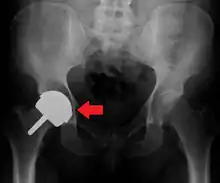

Hemiarthroplasty

Hemiarthroplasty is a surgical procedure that replaces one half of the joint with an artificial surface and leaves the other part unchanged. This class of procedure is most commonly performed on the hip after an intracapsular fracture of the femur neck (hip fracture). The procedure is performed by removing the head of the femur and replacing it with a metal or composite prosthesis. The most commonly used prosthesis designs are the Austin Moore and Thompson prostheses. A composite of metal and HDPE that forms two interphases (bipolar prosthesis) can be used. The monopolar prosthesis has not been shown to offer any advantage over bipolar designs. The procedure is recommended only for elderly/frail patients, due to their lower life expectancy and activity level. This is because over time the prosthesis tends to loosen or to erode the acetabulum.[84] Independently mobile older adults with hip fractures may benefit from a total hip replacement instead of hemiarthroplasty.[85]

Hip prosthesis for hemiarthroplasty. This example is bipolar, meaning that the head has two separate articulations.